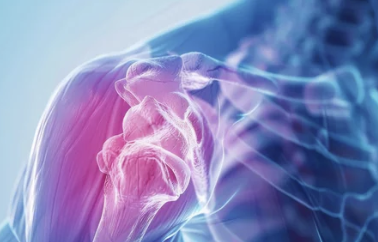

- 증상: 쇄골 골절이 발생하면 어깨와 목 부위에 심한 통증이 생기고, 팔을 움직이기 힘들어져요. 골절 부위가 붓거나 멍이 들기도 하고, 뼈가 비정상적으로 튀어나온 것처럼 보일 수 있어요.

쇄골 골절 후에는 뼈가 잘 붙더라도 어깨와 팔의 기능이 약해져 있어요. 그래서 재활 운동을 통해 근육을 강화하고 관절의 움직임을 회복하는 과정이 필요해요.

- 초기 재활 운동: 회복 초기에는 간단한 스트레칭과 관절의 가벼운 움직임으로 시작해요. 무리하지 않는 범위 내에서 어깨와 팔을 천천히 움직여줍니다.

- 근력 강화 운동: 뼈가 완전히 붙은 후에는 본격적인 근력 강화 운동이 필요해요. 가벼운 저항 운동을 통해 어깨와 팔의 힘을 되찾을 수 있어요.